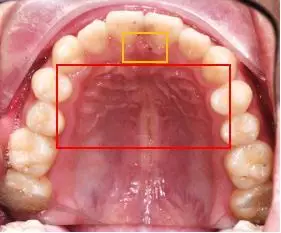

口腔内部,牙齿旁边的口腔上,长了两个红色血包.

口腔内部 这是什么情况

不知道是口腔溃疡还是啥?也不疼,反正就是可以感觉到里面的肉烂了